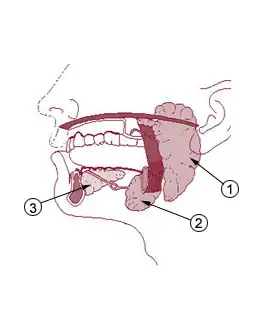

| As glândulas salivares maiores: a glândula parótida (1), na qual se forma a maioria dos tumores de glândula salivar, a glândula submandibular (2) e a glândula sublingual (3). | |

A neoplasia de glândula salivar é um tipo de câncer que se forma nos tecidos de uma das glândulas salivares, as quais são classificadas em "maior" e "menor". As glândulas salivares maiores compreendem as parótidas, a submandibular e as sublinguais. As glândulas salivares menores são glândulas secretoras de muco encontradas no palato e nas cavidades nasal e oral.[1] O câncer de glândula salivar é raro, representando 2% dos tumores de cabeça e pescoço, sendo que a maior parte acomete as parótidas.[2]